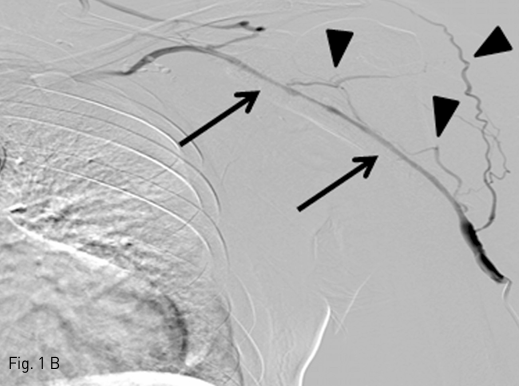

Fig 1B

B. A venography shows diffuse long-segmental, high-grade stenosis in cephalic vein (arrows) with multiple collateral veins (arrowheads).